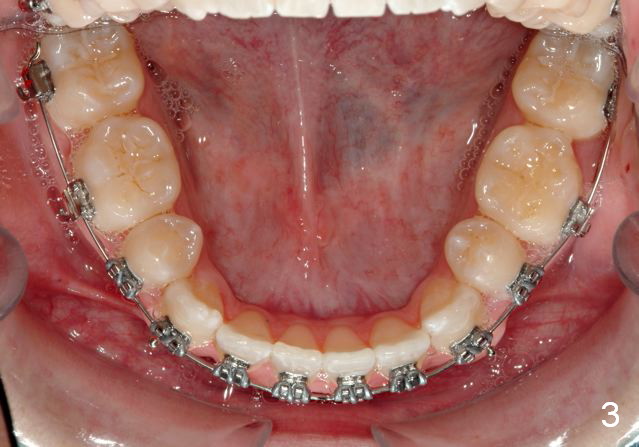

Initial bonding on 08/04/2014 (Fig.1-3); follow up appointments (09/20/2014 (Fig.4,5); 11/11/2014 (Fig.6,7), prepared for maxillary segmental surgery to expand, advance, and level.

I routinely start off with a round NiTi AW, like .014 in the .018 slot, then to .016 and up to 16X22 NiTi. Then I go to rectangular SS.  I segmented the AW to facilitate the surgery.

Mine are crimpable. Very convenient, you just squeeze them onto the AW right where u want them. I provide them for the oral surgeon for jaw surgery cases.

Thanks.  It is my understanding that preop ortho is to decompensate, in your case, make anterior cross bite worse so that there is more room to correct the cross bite.  In fact the lower continuous AW does work toward my dream goal.  How to correct proclined upper anteriors?

Your understanding is spot on!